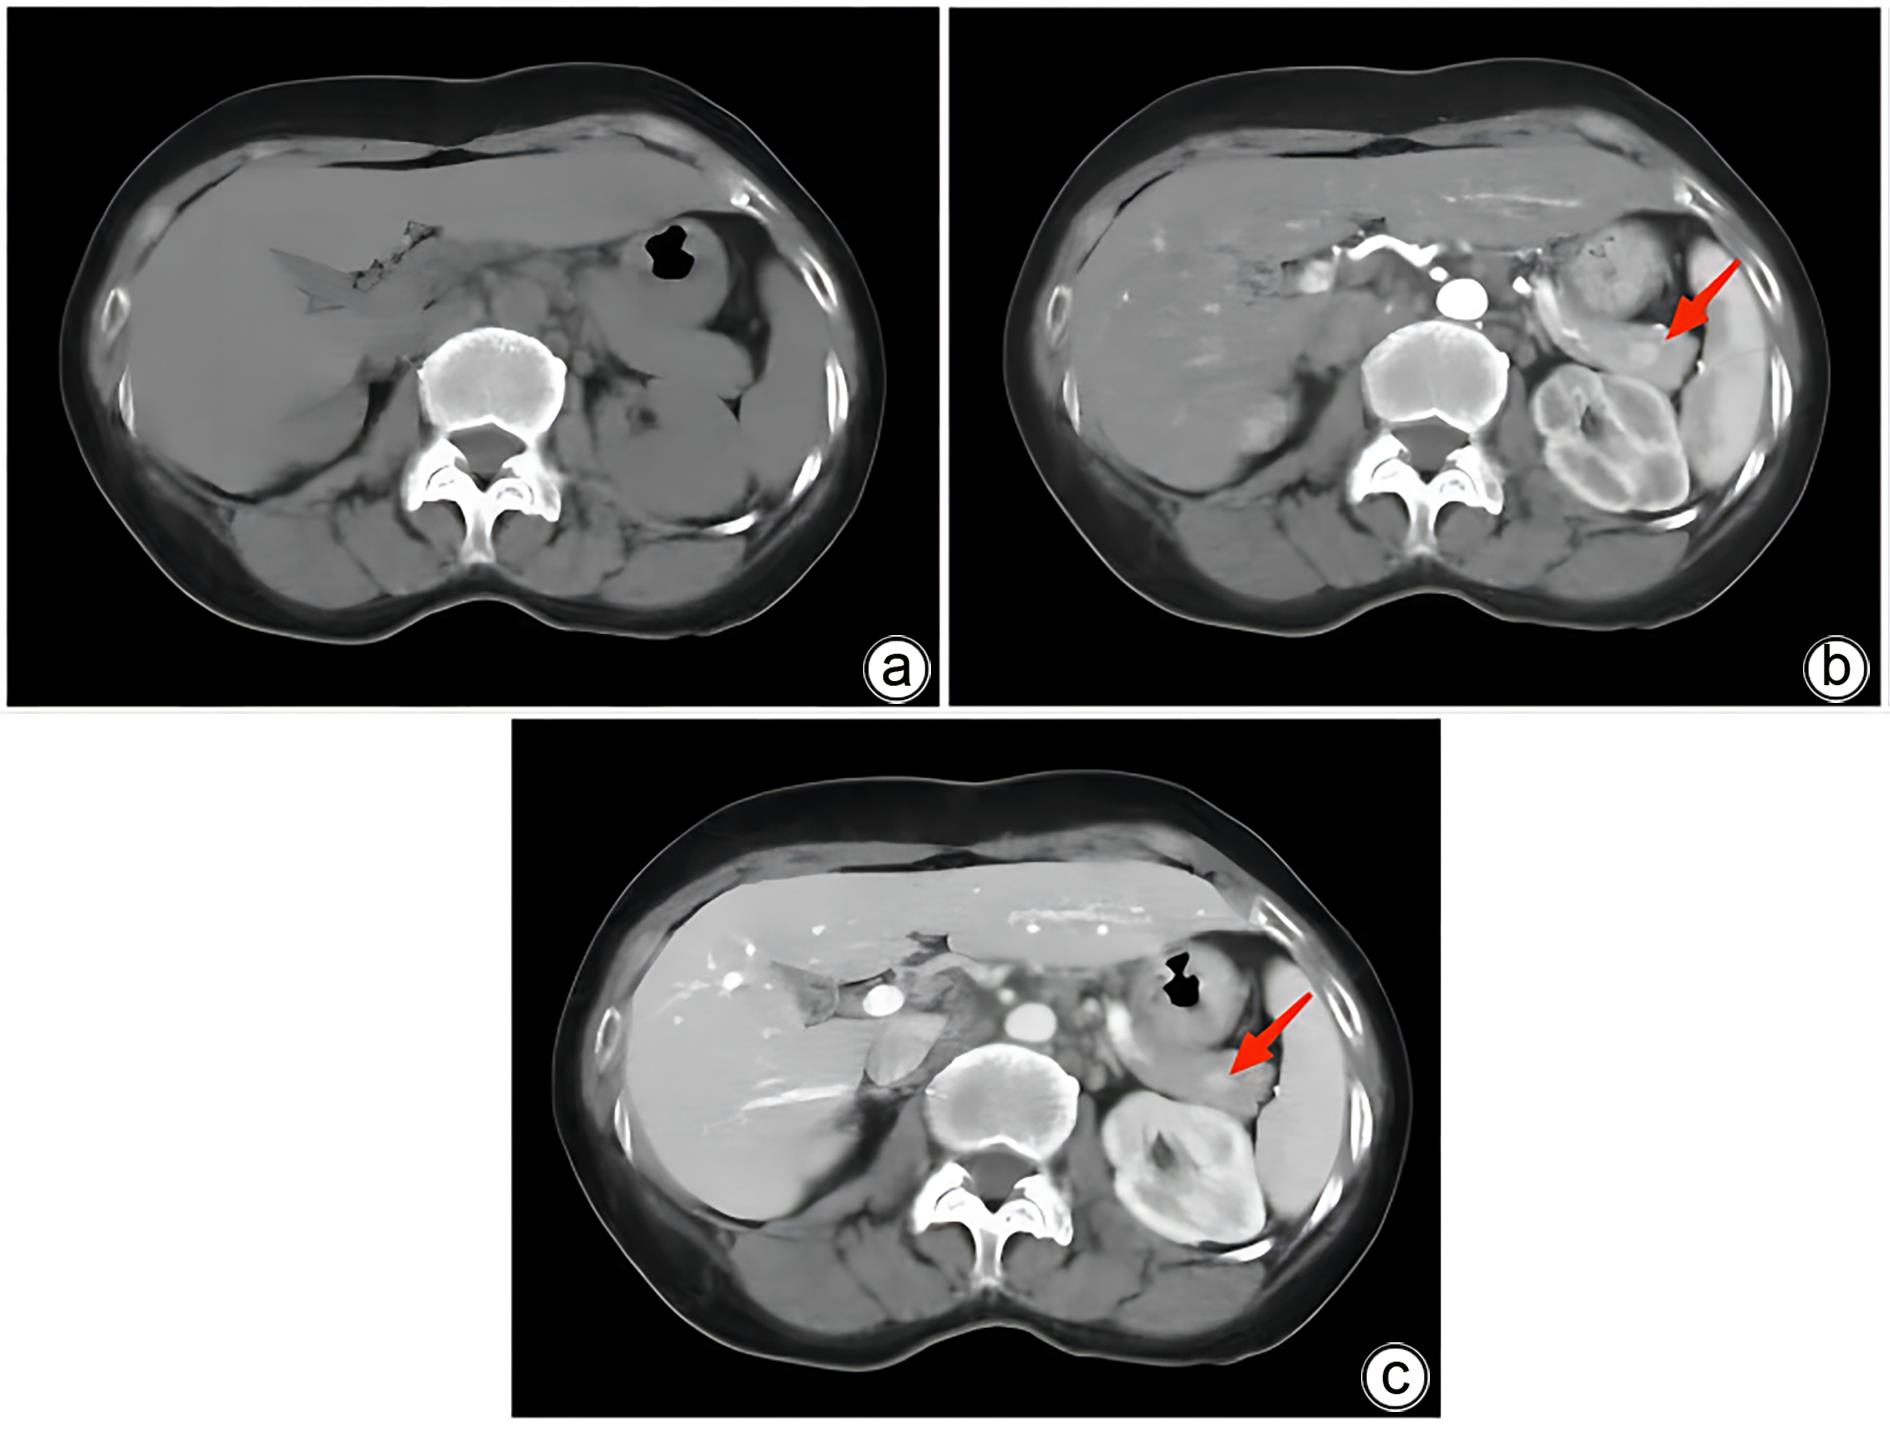

胰腺内副脾误诊2例报告

2024, 40(2): 365-368. DOI: 10.12449/JCH240223

摘要(1364) HTML (331) PDF (1188KB)(157)

摘要:

副脾是指正常脾脏以外存在的,与主脾结构相似,有一定功能的脾脏组织,其中完全被胰腺包裹的胰腺内副脾(IPAS)发生率仅为2%,因其临床症状不典型,影像学特征与胰腺神经内分泌肿瘤、胰腺实性假乳头状瘤以及其他胰腺占位性病变较为相似,临床上容易误诊。本文报道了2例分别被误诊为胰腺神经内分泌肿瘤和胰腺实性假乳头状瘤的IPAS患者,并分析误诊原因,总结诊疗经验,以期提升临床对IPAS明确鉴别诊断的认识。